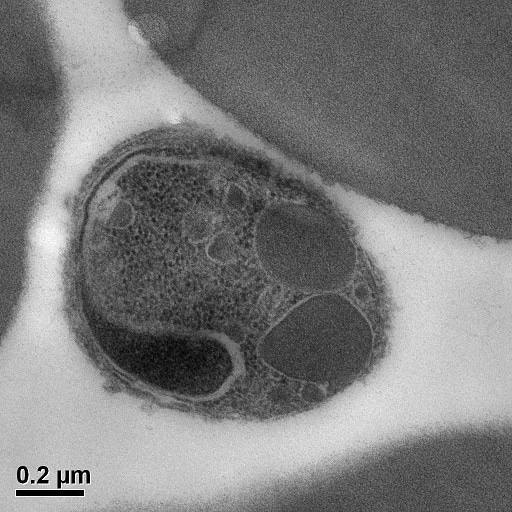

Malaria merozoite attached to a human red blood cell prior to invasion (electron microscopy)

Naturally-acquired immunity to malaria develops after repeated infections, and the observation that immunity can develop has long-provided a strong rationale that effective vaccines against malaria are achievable. It is during blood-stage of infection that clinical malaria and severe disease occurs, and a key target of vaccine development is the merozoite form of P. falciparum, which invades human red blood cells and replicates inside them. However, new insights into the targets of immunity to malaria are urgently needed to advance more effective strategies in vaccine development.